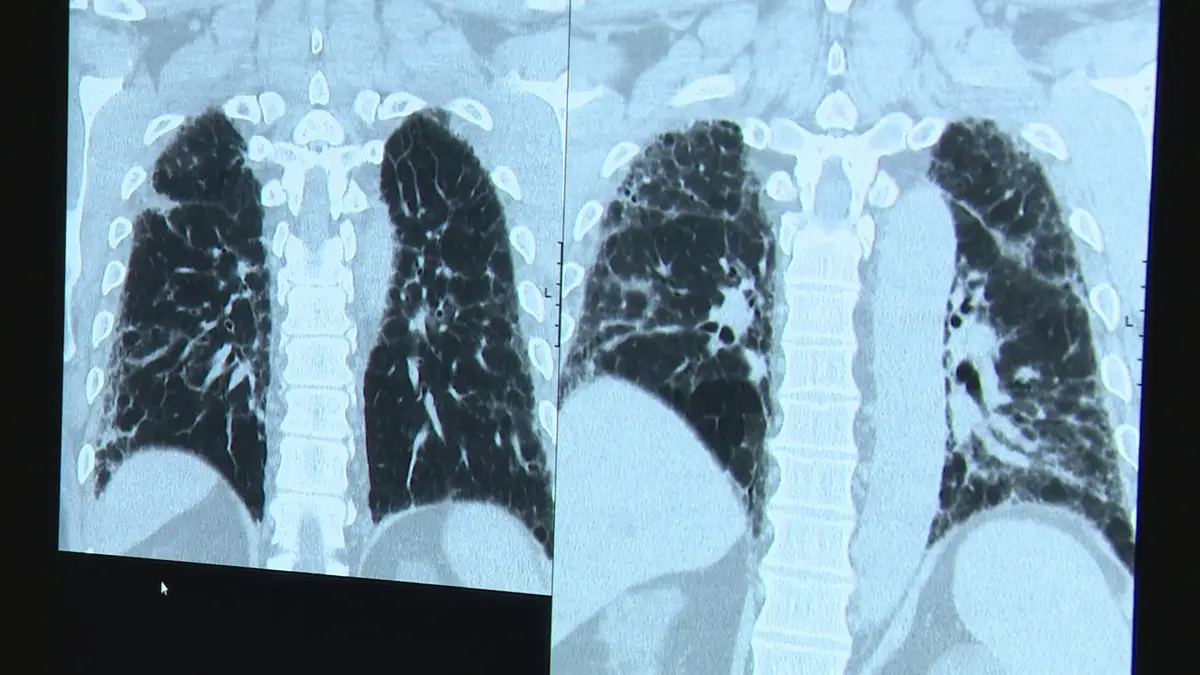

Portugal tem agora o primeiro registo de doentes com fibrose pulmonar

Há meio ano foi criado um biobanco, no Hospital de S. João do Porto, que recebeu até agora cerca de 60 amostras biológicas. Os dados são diariamente apontados para o primeiro registo português de doentes com fibrose pulmonar.

A fibrose pulmonar tem um elevado impacto na vida dos doentes. A taxa de mortalidade é mesmo comparável a alguns tipos de cancro e é uma das principais causas de transplante pulmonar em Portugal e no mundo.